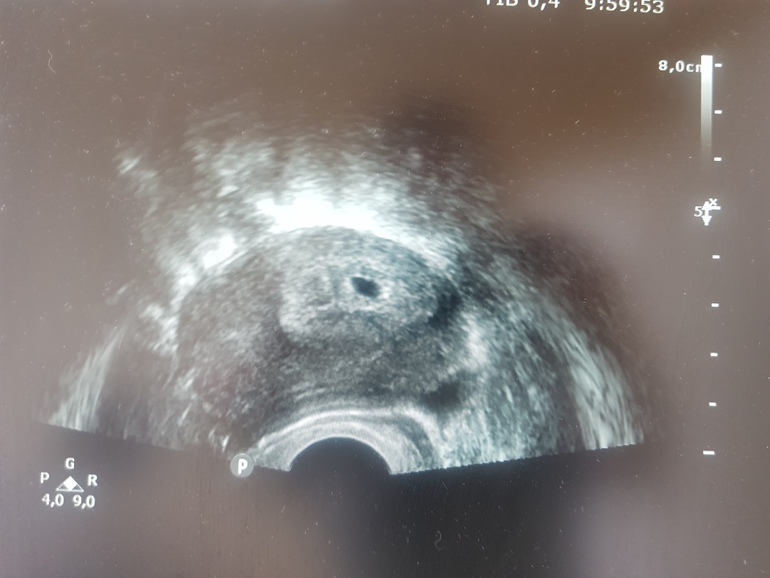

Пол малышаЕсть знатоки? 😄 Кто понимает этот метод, на кого больше похож, на мальчика или девочку?🤔

УЗИ абдоминальное, через живот. Срок 7+3

УЗИ через живот. Я уже запуталась в этом методе. Одни пишут что если вагинально,то слева это мальчик,а справа девочка. А если УЗИ было через живот то слева девочка,а справа мальчик. То есть наоборот. У меня УЗИ через живот, эмрион справа, выходит должен быть мальчик. Хз, посмотрим в 12 недель что скажут 😄